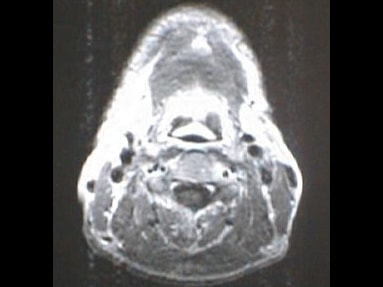

中咽頭末期がんMRI画像③

入院当時MRI画像③

中咽頭末期がん消滅時MRI画像③

入院3か月後癌消滅MRI画像③